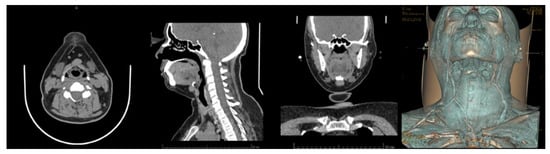

3.3. Case 3. Adjustable Navigation Frame

Operating Principle and Conclusion